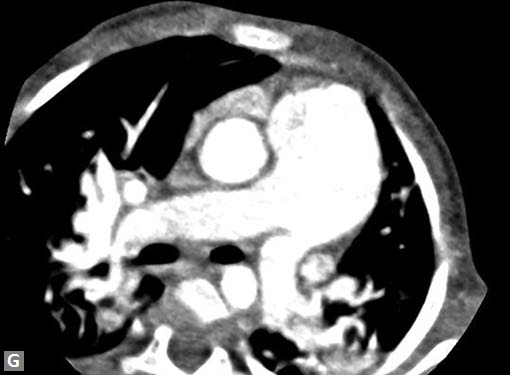

Pericardial effusion may accompany type A dissection.

Hemopericardium is the dreaded complication of leaking

type A dissection (Figs 19S to V). The type B dissection can

cause small foci of atelectasis in adjacent lungs and should

not be mistaken for leak. Type B dissection can leak and cause

left hemothorax.

Figs 19A to Y (A to C) Scannogram (A), plain (B) and contrast study (C) show partial anomalous pulmonary venous connection; (D to F) Heterotaxy; (G) Aortic occlusion; (H and I) Aortic stents; (J) Aortic dissection with ‘Benz’ sign due to second dissection within the true lumen; (K, L and M) Aortic dissection with thrombus in pseudolumen following catheter angiogram; (N) Aortic dissection involving common carotid arteries and subclavian artery; (O, P, Q and R) Aortic dissection with right renal artery arising from true lumen and left renal artery from false lumen; (S, T, U and V) Stanford B dissection with extension Y to iliac vessels; (W to Y) Aneurysmal dilation of ascending aorta